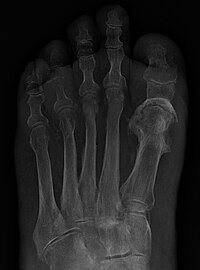

Osteomyelitis of the 1st MTP.jpg

Паронихия пальца Панариций Бородавка на пальце Деформация ногтей Остеомиелит. Разрушение костей и костного мозга